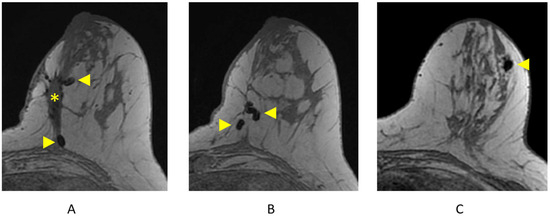

2.4.7. Identifying Lymph Nodes

3.1.5. Evaluation of Axillary Lymph Nodes

3.1.6. Evaluation of Internal Mammary Lymph Nodes (IMLNs)